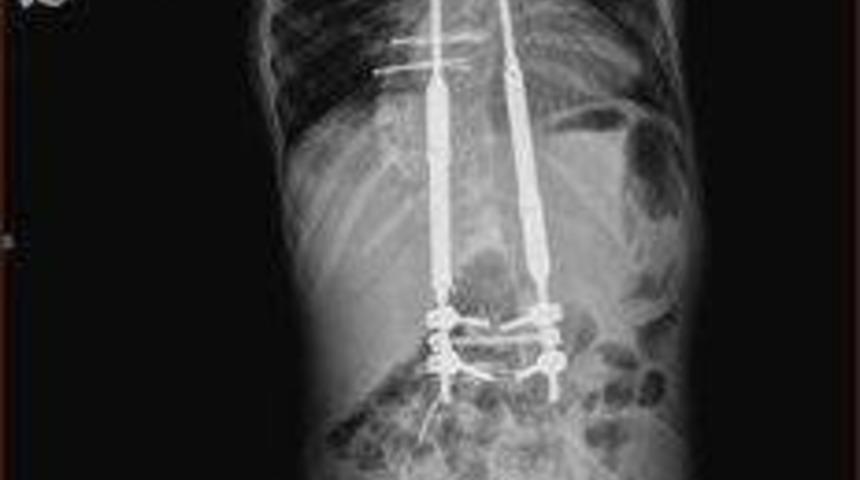

Skolyoz (omurga eğriliği) hastalığı tedavisinde geliştirilen yeni ameliyat tekniğinin, Karadeniz'de “ilk kez” Medical Park Samsun Hastanesi’nde uygulandığını söyleyen Prof. Dr. Nedim Karaismailoğlu, “Medical Park Hastanesi’nde skolyoz (omurga eğriliği) tedavisi gören 7 yaşındaki Yusuf Şahin, Türkiye'de yeni yapılmaya başlanan, omurga eğriliği için yeni geliştirilen ameliyat tekniği ile operasyona alındı. 4 saatlik bir operasyon ile 20 cm uzunluğunda ‘uzayan platin’ adı verilen bir alet takıldı” şeklinde konuştu.

Bu tekniğin Türkiye'de son 6 aydır uygulandığını ifade eden Prof. Dr. Nedim Karaismailoğlu, “Bu yeni yöntem çocuğun büyümesine ve eğriliğin giderek azaltılmasına müsaade ediyor. Tekrar ameliyata gerek olmadan 3 ayda bir hasta geliyor. Ameliyat yapılmadan bir makine yardımı ile içteki parçanın uzaması sağlanıyor ve çocuğun konforu artıyor. Bu yöntem, hastalar için umut ışığı oldu" ifadelerini kullandı.

Ortopedi ve Travmatoloji Uzmanı Prof. Dr. Nedim Karaismailoğlu, omurga eğriliği tedavisi gören hastaların her 6 ayda bir, 6 saat süren ameliyata girdiğini, yeni geliştirilen bu yöntem ile 4 saatlik ve daha küçük bir operasyon sonucunda hastaların sağlıklarına kavuştuklarını söyledi.